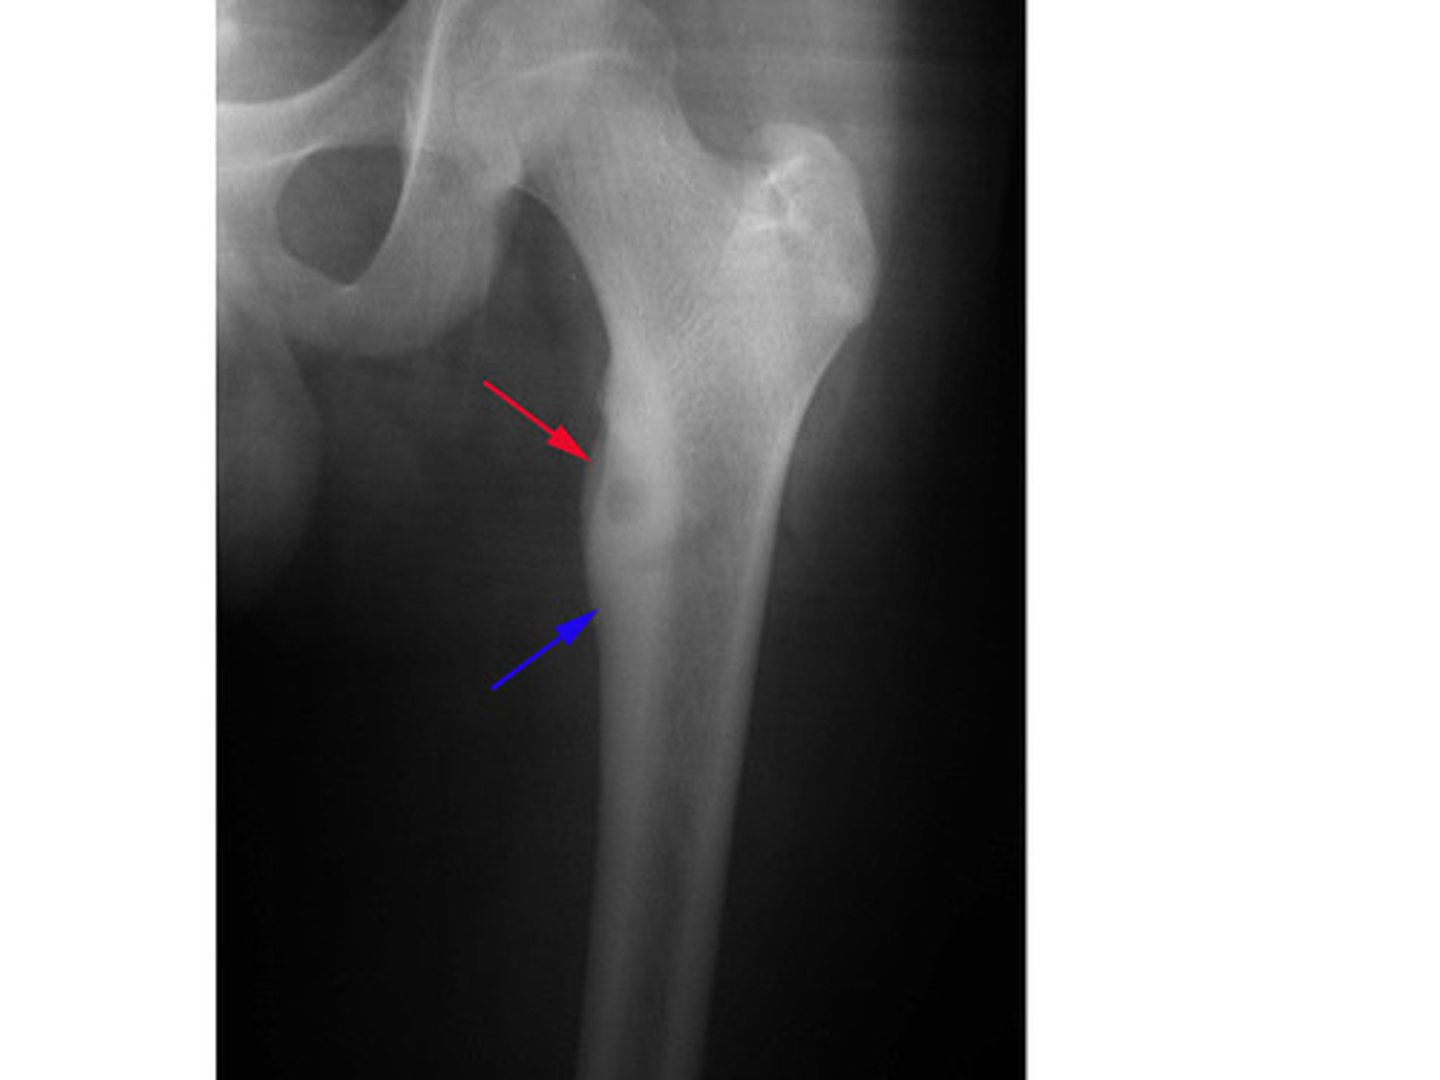

__ sclerotic, cortical lesion on imaging with central nidus of lucency on X-ray. Pain worse at night, unrelated to activity. Pain quickly relieved by NSAIDs.

Osteoid osteoma